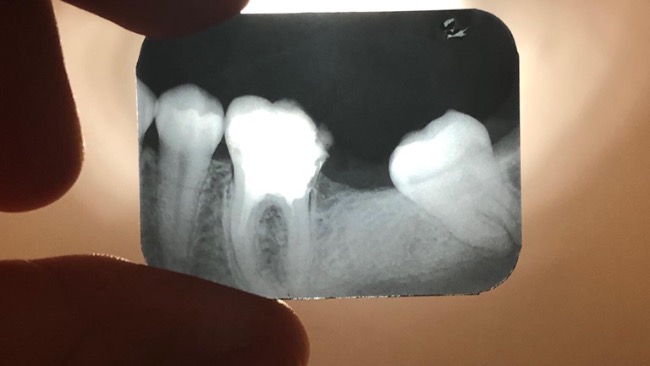

Jedyna nadzieja, aby moc nadal cieszyć się pięknym uśmiechem - leczenie kanałowe. I nagle myśl „Kamień z serca.. Przecież to w tych czasach normalne. Jest szansa!”

Jednak radość nie trwała zbyt długo. Początkowo kosztowne leczenie u jednego dentysty, potem ponownie u drugiego i ciągle ta sama diagnoza - „Bardzo ciężkie kanały do opracowania. Nie jesteśmy w stanie Pani pomóc. Proszę poszukać nowego lekarza” doprowadziło tylko do wyrzucenia pieniędzy „w błoto” , które i tak nie przyniosło pożądanego celu.

(Na zdjęciach widać brak już jednego zęba (7). Kanały nie są dostatecznie wypełnione do końca.)